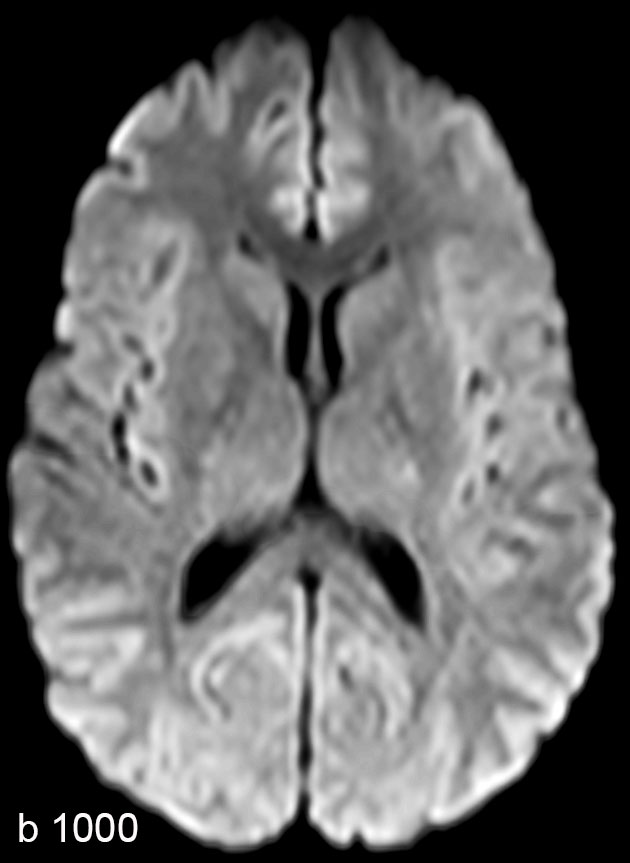

Brain imaging using ComforTone